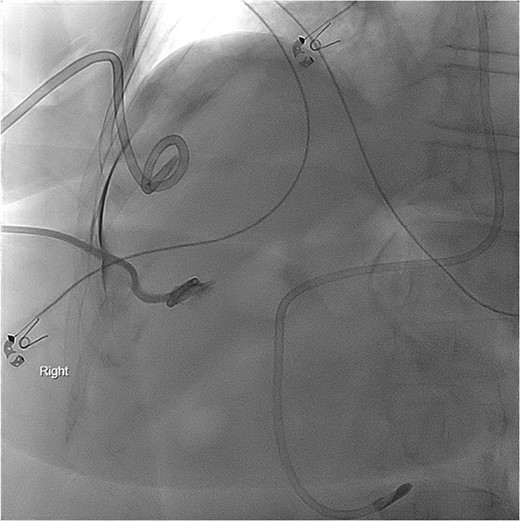

Given her surgical history, duration of symptoms, and active chemotherapy, she was deemed high-risk for intraoperative biliary injury and poor wound healing. Cholecystectomy was deferred and the gallbladder was decompressed with PCT placement. The patient demonstrated significant symptomatic improvement, diet was advanced, and she was discharged home on hospital Day 5. Several hours after discharge, she returned due to lethargy and was found to be in septic shock. Repeat imaging revealed a dislodged PCT. She was admitted to the surgical intensive care unit (ICU) for vasopressor support and mechanical ventilation. Cholangiogram was performed and revealed the pigtail catheter in the peritoneal space (Fig. 2). Under fluoroscopic guidance, the pigtail catheter was replaced without difficulty. She was started on antibiotics for bacteremia and remained in the ICU for management of septic shock and acute hypoxic respiratory failure.

PCT check using fluoroscopy showing retracted tube in the peritoneal fluid.